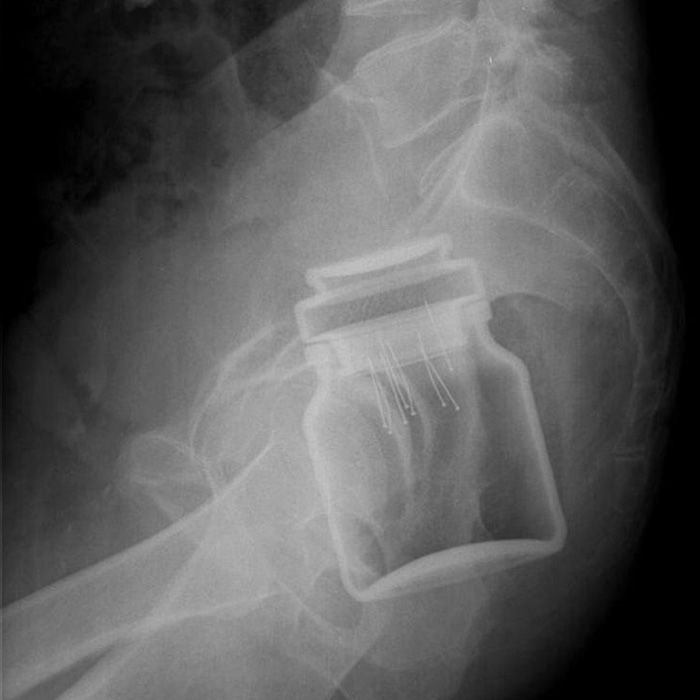

Here are some xrays from unfortunate doctors…

Dr Frank Gaillard

This first image is deceiving. But it’s actually a can of instant coffee. I have no idea what the little pin-looking things are.